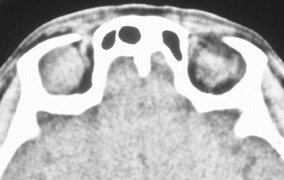

HISTORY AND PHYSICAL EXAMINATION A wide range of signs and symptoms may alert the ophthalmologist to involvement of the orbit by a pathologic process. These include proptosis or globe displacement; compressive optic neuropathy with visual field or visual acuity loss; refractive changes such as progressive hyperopia, restricted eye movements, and diplopia; optic disc changes, including pallor or edema; and fundus changes such as choroidal folds. These manifestations may be the consequences of a primary intraorbital disease or may occur secondary to involvement of the orbit by a process extending from the overlying soft tissues, periorbital sinuses, or intracranial cavity. All patients with suspected orbital pathology should have a thorough ophthalmic history and physical examination. Detailed questioning about the nature, onset, and progression of the chief complaint is necessary to formulate a differential diagnosis. Previous ocular and general medical history related to diseases, operations, medications, and family history should be obtained. A general review of systems will identify risk factors for related systemic diseases, such as hyperthyroidism, metastatic cancer, or lymphoma. A complete examination of the eye and periocular tissues is essential. Abnormal protrusion or displacement of the globe, extraocular motility disturbances, soft-tissue changes, and decreased corneal or periorbital cutaneous sensation should be specifically sought. Special attention always should be directed to evaluation of optic nerve function. Visual acuity testing alone is not sufficient because visual acuity often is preserved initially in patients with compressive optic neuropathy. All patients should be examined closely for detection of an afferent pupillary defect, abnormal color vision, or loss of contrast sensitivity. Formal perimetry should be performed to rule out peripheral field loss. If the presentation has been gradual, evaluation of old photographs may help establish the time course of the pathologic process. In selected cases, appropriate blood work to help identify orbital inflammatory or neoplastic processes also should be obtained. ORBITAL IMAGING Valuable information about the nature and extent of an orbital pathologic process is provided by imaging studies such as computed tomography (CT) scan, magnetic resonance imaging (MRI), and orbital echography. Better spatial resolution, ready accessibility, and lower cost make CT the preferred choice for orbital imaging in most cases. Orbital fat provides a natural contrast between most adjacent orbital structures on CT scanning, and orbital bones are visualized well. Computed tomography is essential for evaluation of the orbital bones because they cannot be imaged with MRI. Direct coronal or sagittal images are important to identify the relationship of a lesion to the optic nerve so that the surgical approach can be planned to avoid traversing the optic nerve (Fig. 1). Newer multislice helical CT scanners allow continuous acquisition of data so that a single rapid pass allows formatting in axial, coronal, and sagittal planes. Multislice CT provides shorter examination times with reduced motion artifact and radiation exposure when compared with conventional CT. Magnetic resonance imaging is useful in selected cases, especially when evaluating the orbital cranial junction. Significant bony artifact and a lack of orbital fat in the orbital apex make CT scan resolution of the orbital apex structures poor. Because cortical bone has low signal on MRI, there is no bone artifact when viewing the orbital apex on MRI. The lack of intervening fat in the apex to provide contrast is overcome on MRI because contrast is provided by the individual nuclear characteristics of each tissue so that the orbital apex structures are visualized well. Consequently, conditions that affect the optic nerve and chiasm, such as optic nerve meningioma and glioma, generally are evaluated with MRI rather than CT scan (Fig. 2). Use of a contrast agent such as gadolinium can further enhance the T1 signal intensity of lesions and is particularly helpful in imaging areas where there has been a breakdown in the blood–brain barrier. Because orbital fat produces a bright signal on T1-weighted images, orbital MR usually is performed with “fat suppression” to prevent masking of lesions. However, incomplete fat suppression can produce artifacts that may be misinterpreted as abnormal enhancement. A few other orbital conditions are better visualized with MRI than CT scanning.1–3 Often, organic foreign bodies, such as wood, are not imaged well with CT scan. These foreign bodies often are visible with MRI. However, care must be taken when imaging any metallic intraocular or intraorbital foreign body because the strong magnetic field of the MR scanner may cause the foreign body to shift position and damage surrounding structures. In some tumors and vascular anomalies, high blood flow is appreciated on MRI. This is caused by a lack of signal, known as a flow void, created by blood flowing rapidly through larger vessels. Tumors that originate in the brain and extend into the orbit secondarily, such as sphenoid wing meningioma, also are visualized well with MRI. However, bony detail and calcification within the meningioma are not imaged well. In unusual circumstances such as this, CT scan and MRI may prove to be complementary, and both techniques may be required to fully evaluate the orbital disease process. Orbital echography can provide useful information in the evaluation of orbital disorders. Because each tissue has its own acoustic characteristics, echography can provide a high degree of tissue contrast. Spatial resolution also is quite good. In some situations, echography can provide information not available on CT scan or MRI. These instances include detection and measurement of blood flow4 and intraoperative localization of small foreign bodies.5 Orbital echography requires specialized equipment and a large amount of expertise to obtain the detailed information that is readily available with CT scan or MRI; consequently, its use has decreased. Recent advances in orbital imaging have been summarized by Lee and colleagues.6 |